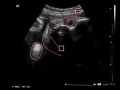

妊娠8ヶ月目 妊娠28~31週の胎児の様子・母体の症状や気を付けること

まだ赤ちゃんが逆子でいる場合も多く、子宮の中を回転したりして遊んでいます。妊娠8ヶ月という時期なら、約8割くらいは頭位にもどります。

妊娠20週前後には、前置胎盤の可能性を指摘されることもあるでしょうが、80%以上は妊娠経過に伴って前置胎盤ではなくなり、最終的に診断されるのは妊娠8カ月30~32週になります。